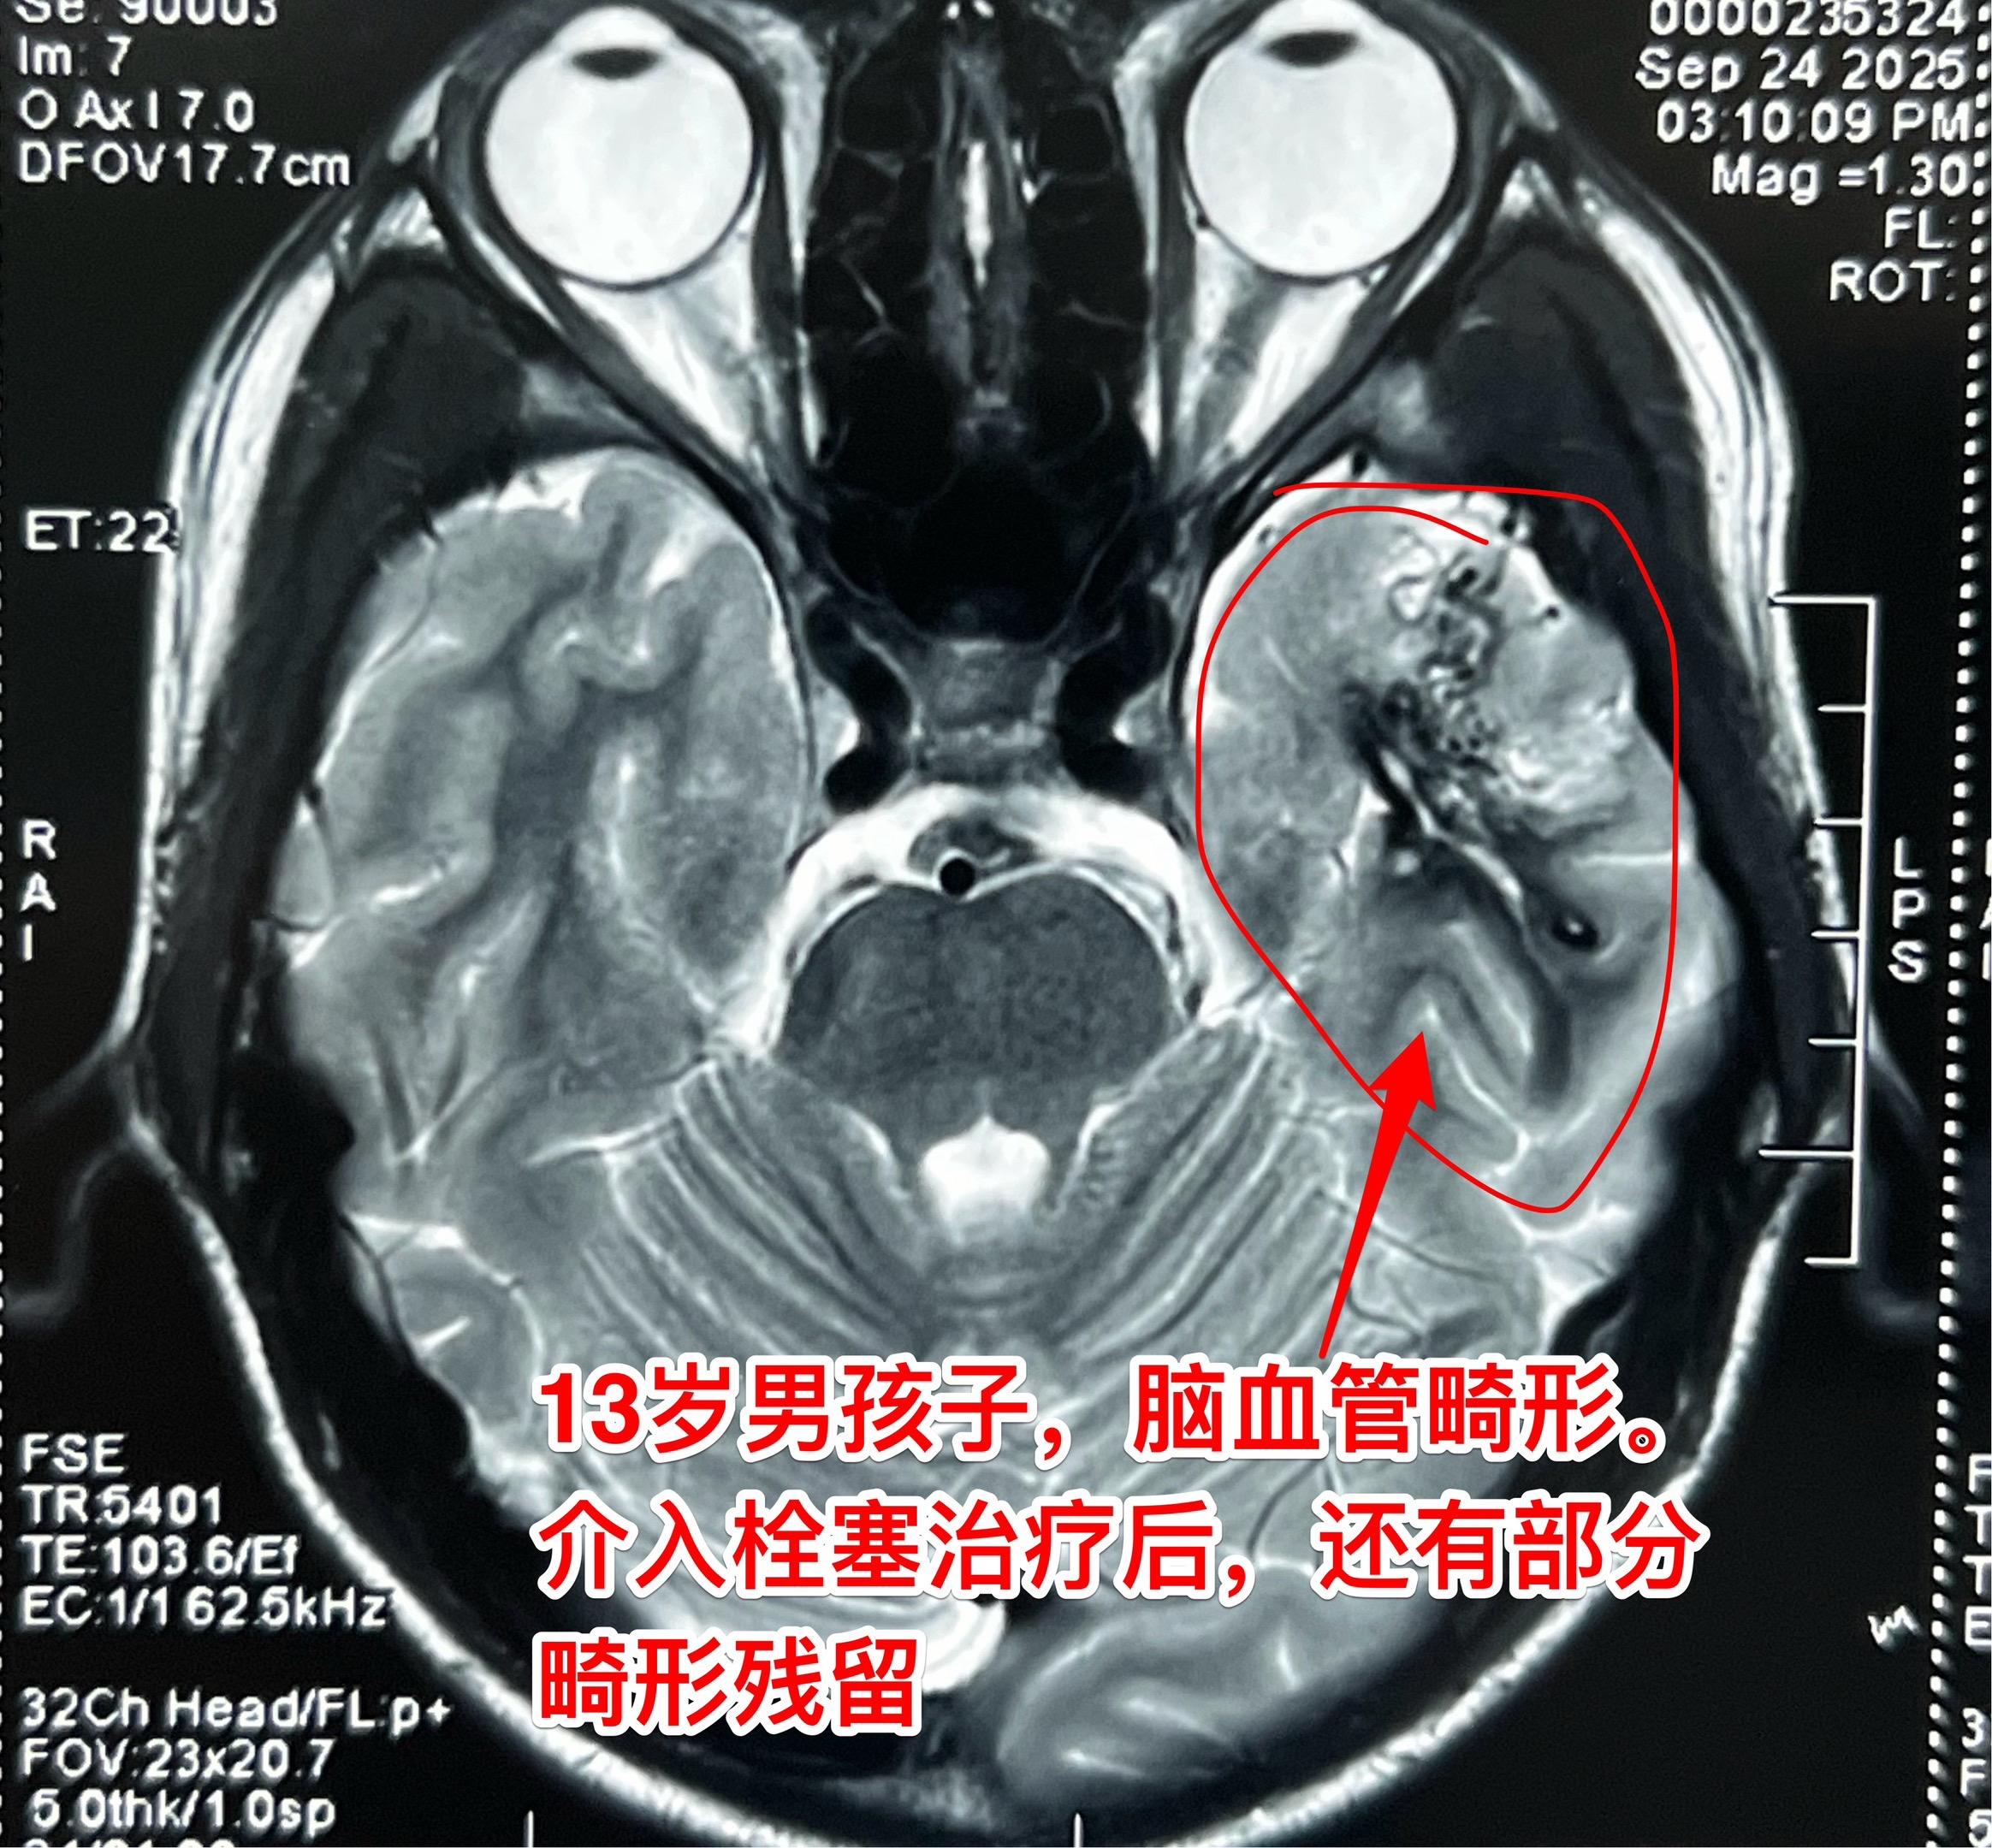

脑血管畸形破裂是青少年最常见的脑出血病因。2025年7月30日,山东省13岁的男孩子突感头痛,到医院去看病,作了头CT检查,发现脑部出血了! 随后医生给他作了脑血管造影检查,发现病因是脑血管畸形。当时作了介入栓塞治疗,脑血管畸形未达到治愈性栓塞。 幸运的是男孩子没有留下任何后遗症。 残留的脑血管畸形不大,采用开刀切除是很有希望获得治愈的。 2025年9月26日在我科作了开颅手术,将血管畸形完全切除。手术后男孩子没有出现偏瘫和失语症状。